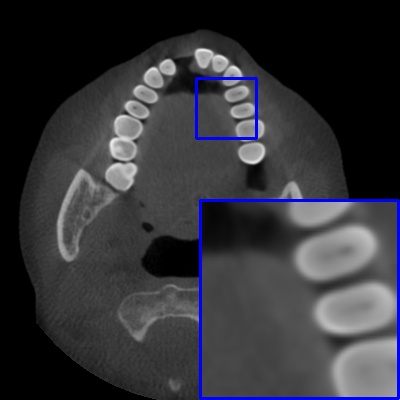

Figure 3: Visual comparison of MAR images by different methods on synthetic MA image. The PSNR (dB)/SSIM results are reported below each image for reference.

Results on synthetic MAR. In Table 1, we provide the quantitative results. One can see that our MARformer-L outperforms the other methods in terms of PSNR and SSIM, but needs only 11.76M parameters and 60.25G FLOPs. Note that the second best method Uformer-B has 50.42M parameters and 205.82G FLOPs. Besides, our MARformer-T achieves similar PSNR and SSIM results with Uformer-T, but needs only 0.40M parameters and 12.82G FLOPs compared to 5.24M and 25.39G for Uformer-T. Our MARformers also achieves faster inference speeds than the Uformers, though with inferior Dice scores, respectively. The qualitative results of visual quality are presented in Fig. 3. We observe that our MARformer-L well recovers the teeth shapes and obtains higher PSNR and SSIM results than the other comparison methods. The light-weight MARformer-L achieves similar results to Uformer-T. All these results validate that our MARformer is more efficient than the comparison methods on dental CBCT MAR.